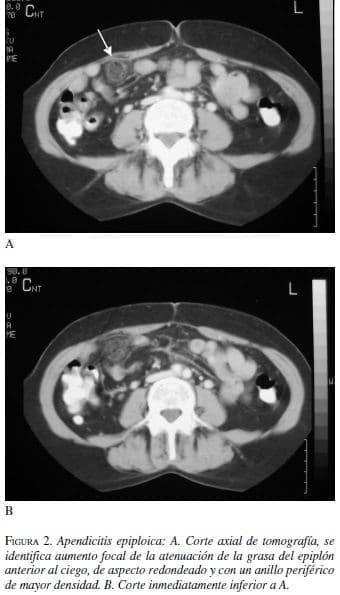

Hombre de 38 años con cuadro de 12 horas de dolor en el flanco y la fosa iliaca derechos, recuento normal de glóbulos blancos pero velocidad de sedimentación y proteína C reactiva ligeramente elevadas. Con impresión diagnóstica dudosa de apendicitis aguda, se realiza tomografía contrastada de abdomen (figura2).

Los apéndices epiploicos son normalmente invisibles en la tomografía a menos que estén rodeados por ascitis. Los hallazgos característicos de apendicitis epiploica son: una masa oval paracolónica con densidad de grasa que representa el apéndice inflamado o infartado, con aumento en la atenuación de la grasa a su alrededor, un anillo hiperatenuante bien definido que rodea a la masa que representa al peritoneo visceral inflamado y en algunas ocasiones un “punto” central de alta atenuación que representa los vasos ingurgitados o trombosados o áreas centrales de hemorragia (3, 8-9).